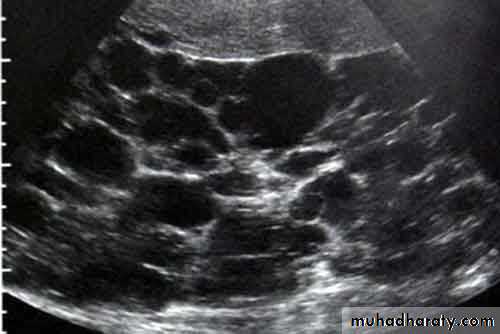

• Multiple simple cysts• Polycystic disease

• Malignant lymphoma

• Metastases

• Inflammatory masses.